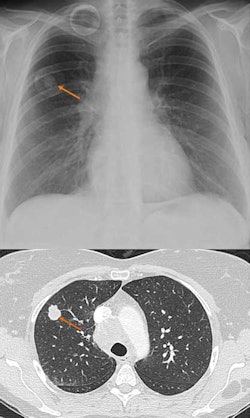

![]() |

| Researchers found CAD to improve sensitivity. |

Of the 165 CAD findings or regions of interest (ROIs) on chest radiography, 49 were actual nodules seen on CTA. No definitive correlation with size of the nodule and CAD detection of the nodule was noted. There were 121 cases where there was no CAD ROI, and the CTA showed no nodules between 5 and 15 mm.

CTA demonstrated no nodule or other abnormality in this region. Specificity was 78% and accuracy was 74%. Five ROIs ranked as either 1 or 2 by the radiologist using CTA were determined to be true nodules.